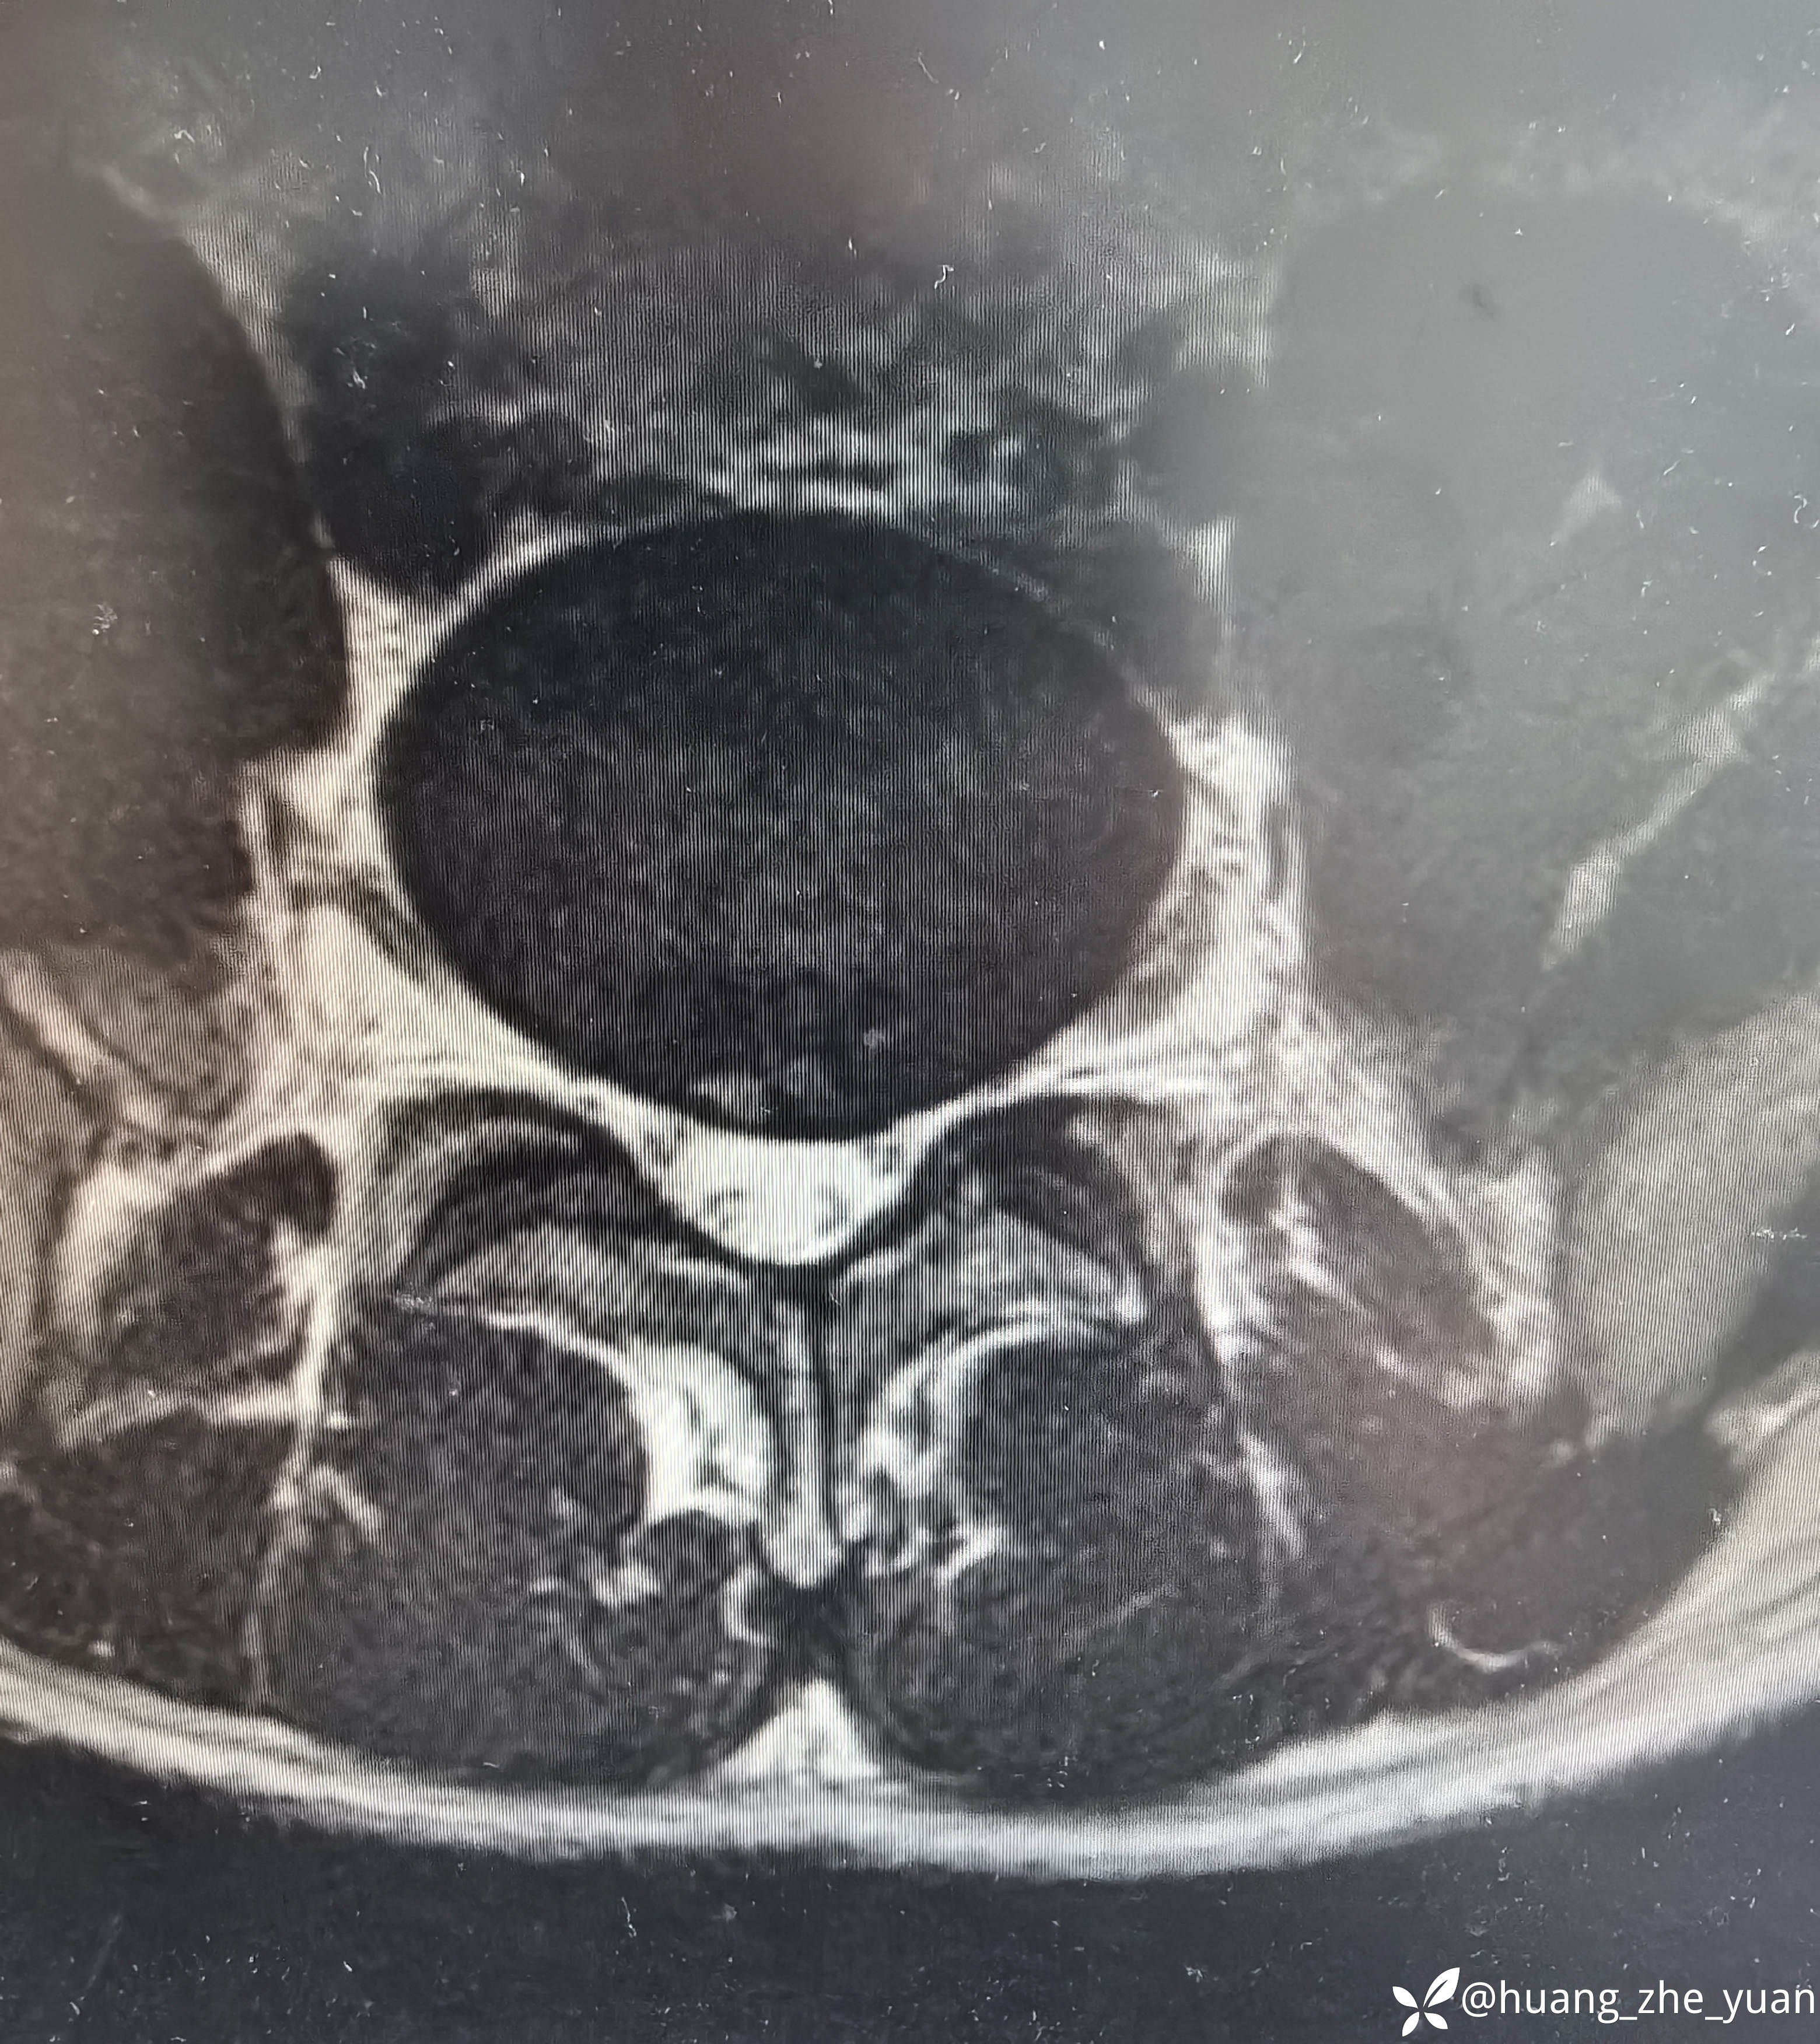

病人20岁,非常年轻,但是腰痛症状很明显,全天24小时无缓解,术前腰痛VAS评分7分,腿几乎不痛。保守治疗无效,融合又太早,和病人沟通后建议内镜下射频消融,术中尽量减少创伤。

局麻单切口做两节。

椎间孔少量成形。椎间盘做微创消融。